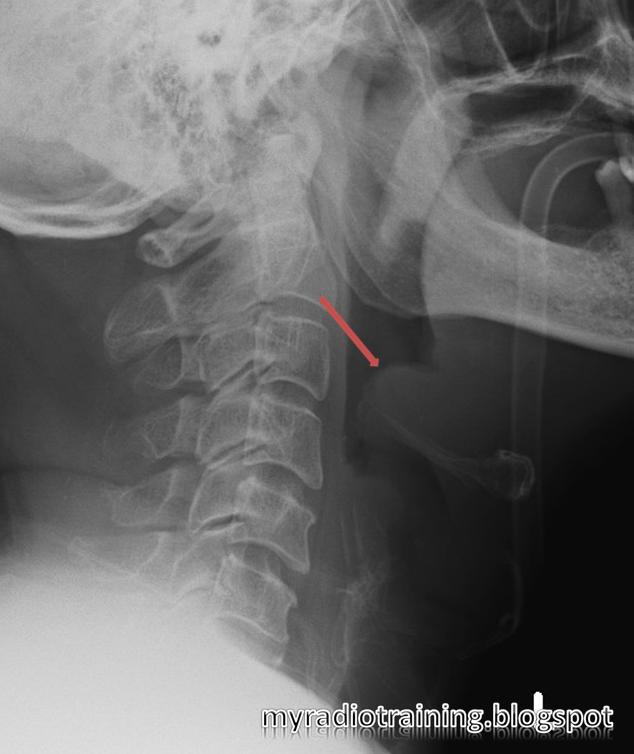

Soft Tissue X-ray Of The Neck Showing Thickening Of The Prevertebral

My Radiology Training Diary: February 2011